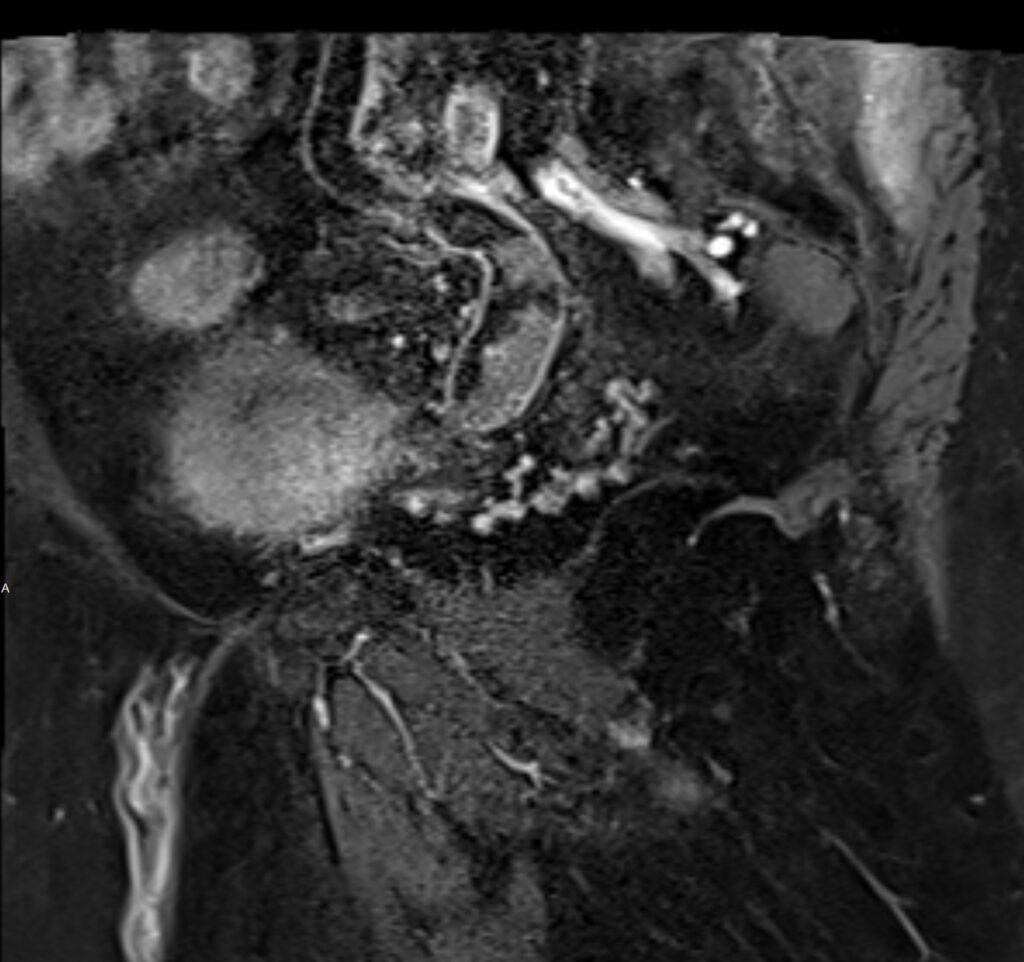

MR images revealed the left dilated ureter and intraluminal polypoidal masses at its distal segment. Associated moderate left hydronephrosis is noted.